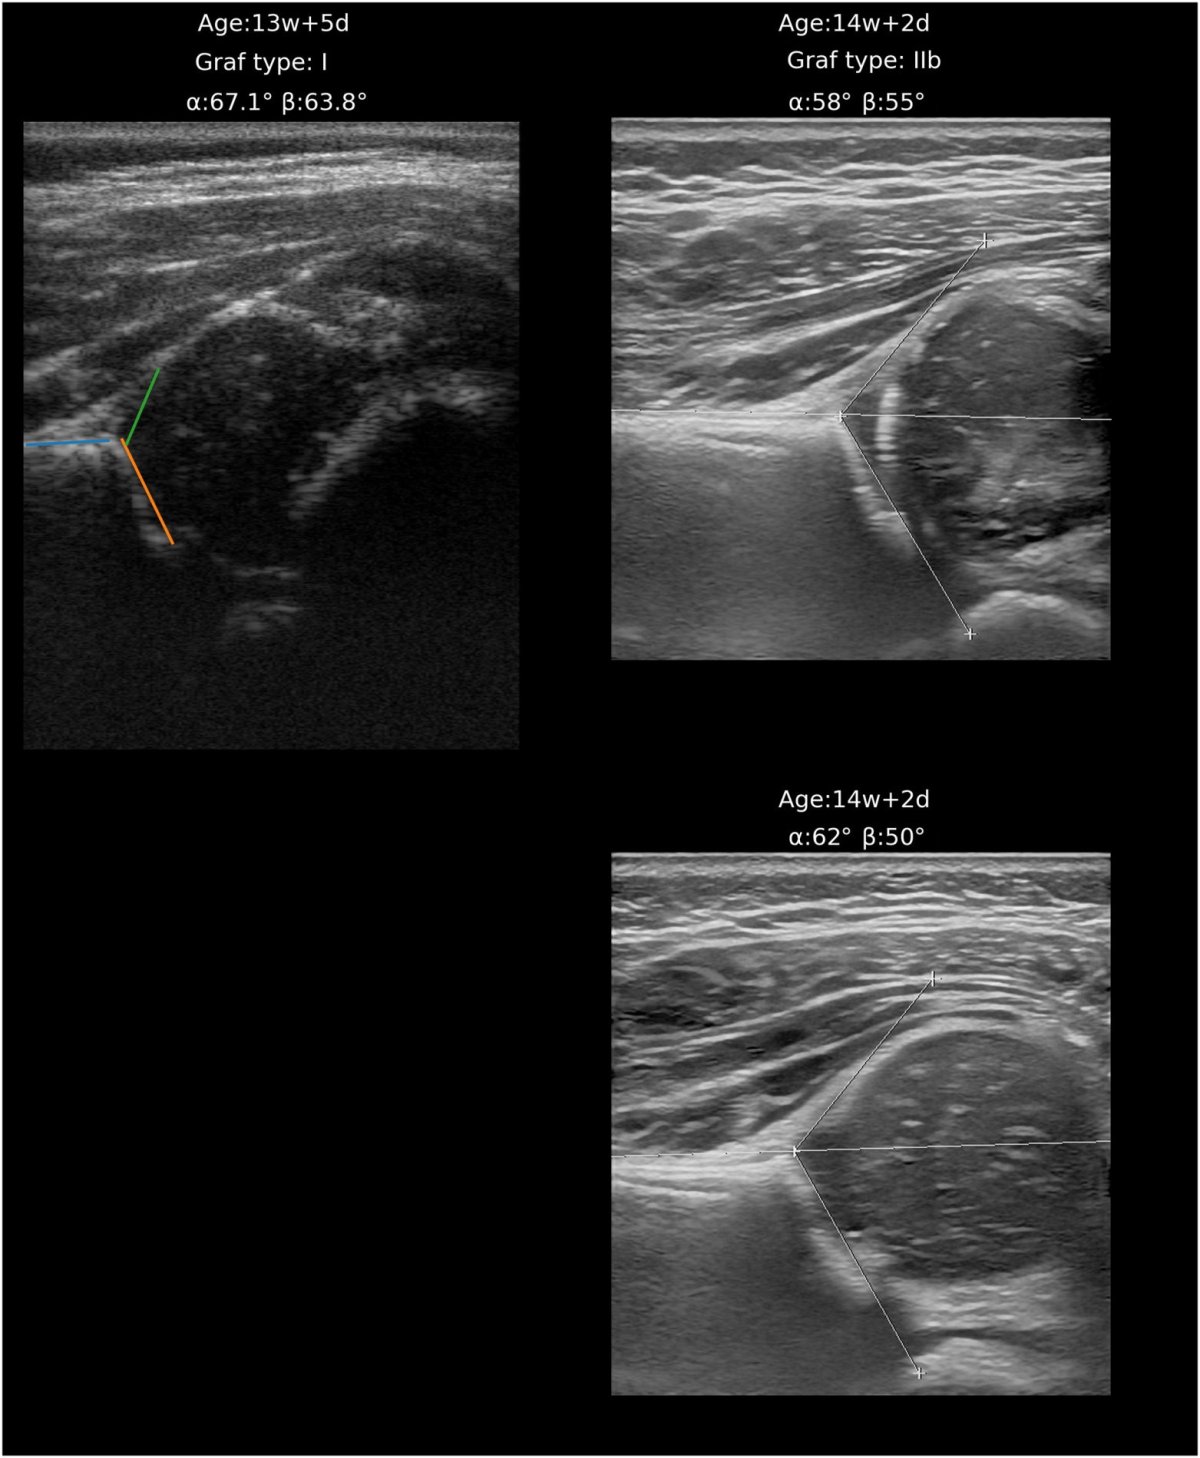

Image source: Verhoeven MMR, Klein WM, De Monye W et al., Computer Methods and Programs in Biomedicine 2025 (CC BY 4.0)

Traditionally, training a sonographer to perform hip ultrasounds takes several months, making the implementation of ultrasound at CHC centers impractical. Researchers from Radboudumc and JGZ Kennemerland have shown that CHC physicians can be trained in just one hour to perform an AI-assisted ultrasound at the CHC center. Consequently, introduction of ultrasound at the CHC center could improve the specificity of the screening program and reduce the number of unnecessary referrals.

In this study, two CHC physicians scanned a total of 105 infants at the CHC center. The AI application’s results were evaluated by two trained radiologists, showing that 56% of infants without DDH could be correctly identified. This means that only 3.5 infants need to be referred to the hospital for an ultrasound to detect one infant with DDH. Therefore, the specificity improves to 92%.